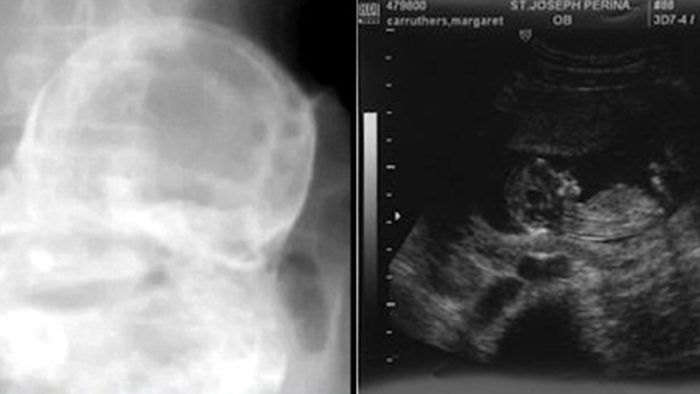

A Brazilian woman in her 80s who went to the hospital with stomach pains had a fetus in her uterus that was 44 years old. A doctor in the central Brazilian state of Tocantins did an X-ray on the woman’s stomach and found a “stone baby.”

The X-ray showed “the face, the bones of the arms, the bones of the legs, the ribs, and the spine” of a baby that died between 20 and 28 weeks.

The baby died, but it didn’t come out of her. When this happens, the fetus is covered in calcium to protect the body from the dead baby. The result is a “stone baby,” which is a medical disease called lithopedion.